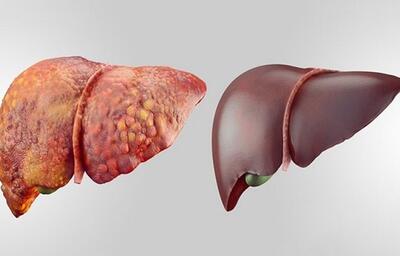

استامینوفن میتواند قاتل کبد باشد

استامینوفن زمانی که بهطور تجویز شده مورد استفاده قرار گیرد حتی برای افرادی که بیماریهای کبدی دارند نیز بیخطر است. با این حال مصرف بیش از حداین دارو بهصورت یکجا و یا استفاده زیاد و مداوم از آن در طول چند روز میتواند باعث مسمومیت کبدی شود.

مصرف بیش از حد استامینوفن برای کبد مضر است

کارشناس امور خدمات بستری و سرپایی سازمان غذا و دارو با هشدار نسبت به افزایش موارد مسمومیت ناشی از مصرف خودسرانه و بیش از حد مسکنها، بر ضرورت آگاهی و رعایت دوز مجاز داروها تأکید کرد.

هشدار درباره همهگیری خاموش کبد چرب

کبد چرب به یکی از بیماریهای شایع در میان مردم تبدیل شده و آمارهای رسمی نشان میدهند که ۴۰ تا ۵۰ درصد از افراد به درجاتی از این بیماری مبتلا هستند.